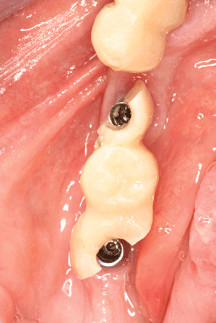

Pérdida de un diente único

La pérdida de un diente único es cuando un solo diente se ha caído o ha sido extraído, y se necesita un implante para reemplazarlo.

Los pacientes pueden notar un espacio donde solía estar el diente. Esta condición puede afectar la estética y la función masticatoria.

El tratamiento incluye la colocación de un implante dental para restaurar el diente perdido.